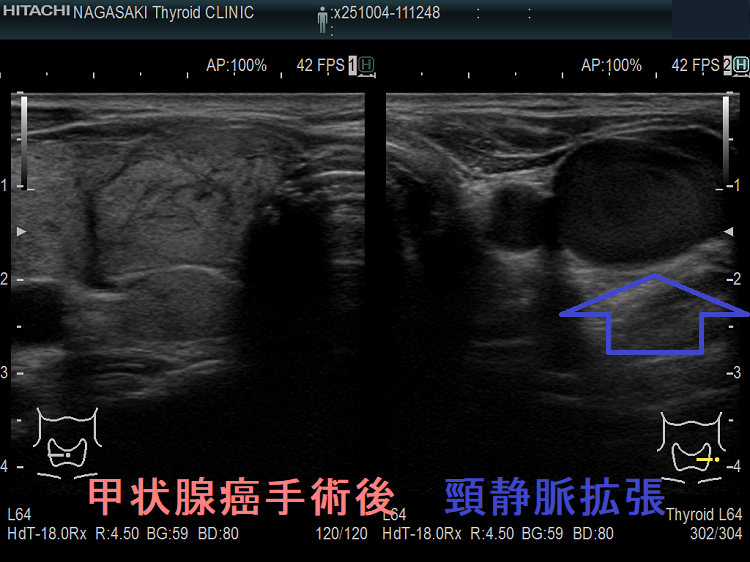

甲状腺癌術後、頸横動脈仮性動脈瘤が生じて破裂する事があります。

報告例は、頚椎後縦靱帯骨化症(OPLL)のため頸部伸展位を取れない状態で外深頸リンパ節を郭清した際、頸横動脈の外膜を傷付け仮性動脈瘤が発生したと推察されます。甲状腺癌手術を終え退院後13日目に頸部痛と左肩甲部から前頸部にかけて腫瘤形成が起きた。画像診断にて頸横動脈瘤とその破裂による大出血と診断し、コ イル塞栓術にて治癒したそうです。(日臨外会誌 67 (10), 2289-2293, 2006)